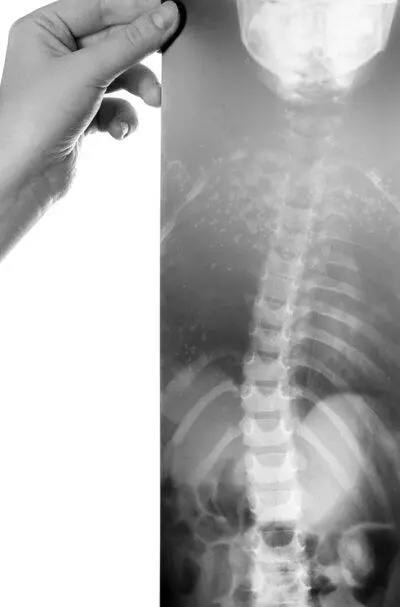

Под сколиозом (от греч. scoliosis — искривление) подразумевают искривление позвоночника во фронтальной плоскости, то есть в правую или левую сторону. Данный вид нарушения осанки может возникать в шейном, грудном или поясничном отделах позвоночника. Когда наблюдается искривление по одной боковой дуге, сколиоз называется простым. Если же искривление позвоночника образуется по нескольким дугам в разные стороны, оно считается сложным. В случае, когда искривлению подвергнут весь позвоночный столб, говорят о тотальном сколиозе. Если появляется только боковой изгиб, то говорят о сколиотической осанке. При этом позвоночник стоящего прямо ребенка выглядит как сплошная дуга бокового искривления и наблюдается асимметрия между правой и левой половинами туловища. Если же одновременно с боковым изгибом происходит поворот позвоночника вокруг вертикальной оси (торсия), то говорят о сколиотической болезни. Этот поворот усугубляет деформацию грудной клетки, вызывая ее асимметрию. В результате внутренние органы смещаются и сжимаются.

Характерный внешний вид ребенка со сколиозом:

♦ голова опущена и наклонена в сторону;

♦ плечи сведены;

♦ спина сутулая;

♦ линя позвоночника дугообразная;

♦ одно плечо выше другого;

♦ асимметрично расположены подмышечные впадины, ключицы, лопатки, талия.